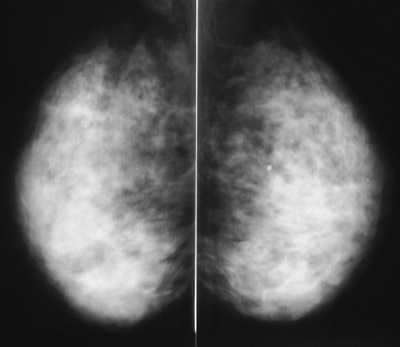

![]() |

| A large cancer is present in the image on the left, but the cancer cannot be seen because it is completely obscured by the dense glandular tissue around it. Note that the breast with the cancer looks exactly like the one without a cancer. The cancer was found here because it was palpable, and was visible on an ultrasound done at the same time as the mammogram. Image courtesy of Dr. Michael Linver. |